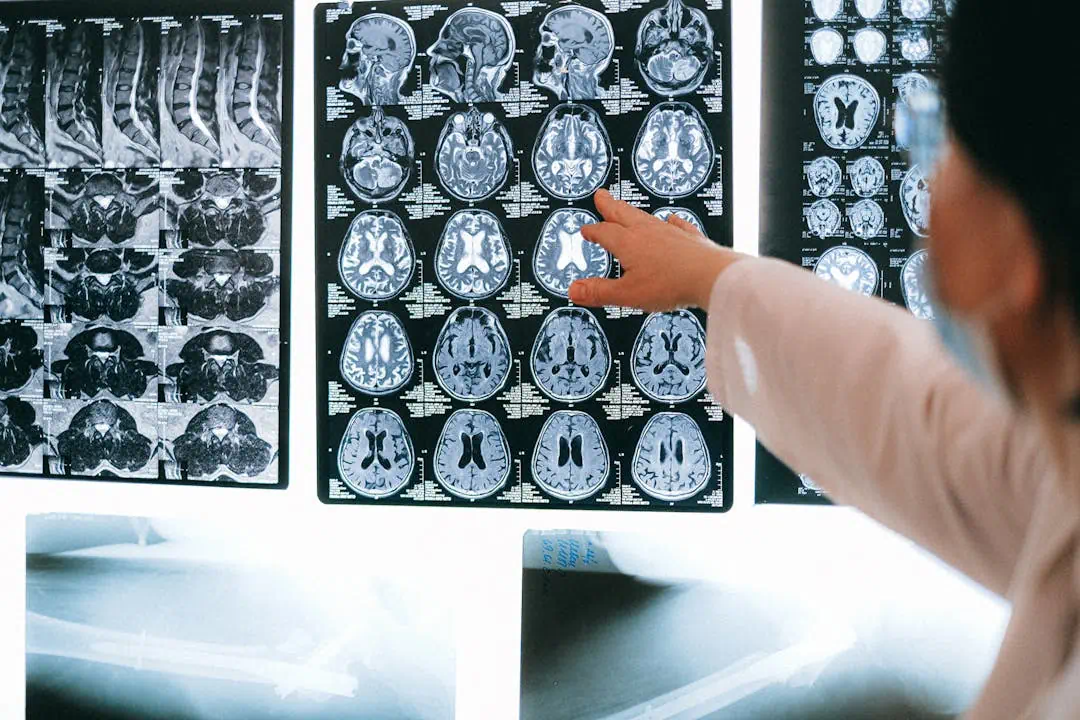

뇌경색 수술하고 있는 의사들뇌경색 수술을 하고 있는 의사의 모습뇌경색 MRI를 확인하고 있는 의사들

뇌경색 초기증상 놓치면 위험합니다